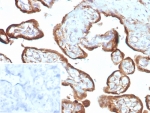

Applications : IHC-P

IMP3 Antibody / Insulin like growth factor 2 mRNA binding protein 3 (clone IMP3/8985R)

Recrabbitmono